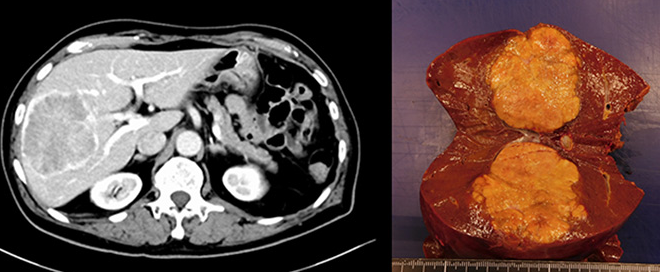

(3) CT/MRI 검사

종양의 위치, 크기, 혈관 침범 여부까지 확인할 수 있어 정밀 진단 및 수술 가능성 판단에 중요합니다.